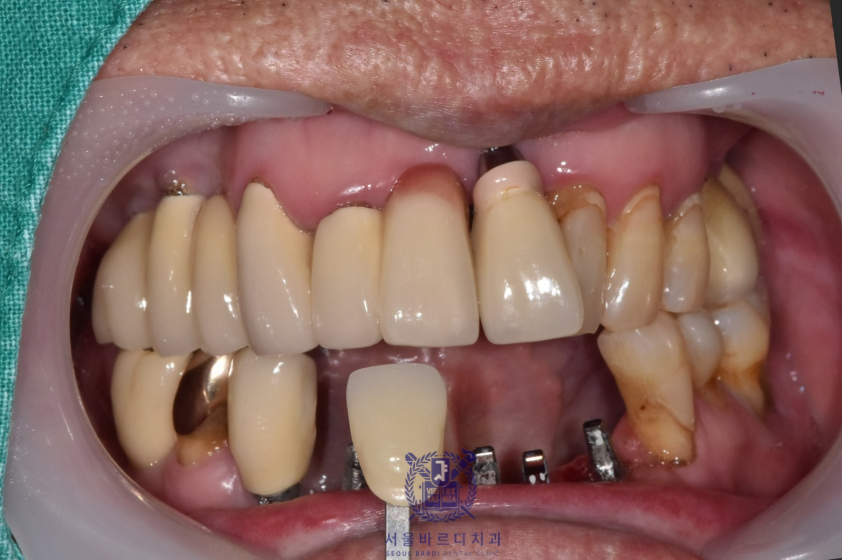

아래 앞니를 발치하게 되면 당분간 치아가 없는 상태로 계실 수 밖에 없어서

임시로 사용하실 수 있는 임시틀니를 만들어드렸습니다.

앞니가 많이 흔들리고 통증이 심했던 터라 최대한 치아를 건드리지 않고

임시틀니를 만들 수 있게 3D 스캐너를 사용하여

스캔 후 제작하였습니다.

이렇게하면 별도의 본 뜨는 과정 없이 편하게 임시틀니를 제작할 수 있습니다.

임시틀니는 뺐다 꼈다하는 디자인으로 불편하시지 않게

최대한 빠르게 제작해드리고 있습니다.

앞으로 새로 할 보철은 깨끗한 색이였으면 한다고 하셔서

앞니는 조금 밝은 색으로 진행하게 되었습니다.

아래 컬러에 맞춰 기존에 있는 보철들도 추후 차례대로 교체하기로하셨습니다.

앞니는 기능적이면도 있지만 심미적인 측면이 매우 중요하기 때문에

최대한 환자분에게 적합한 형태로

환자분의 의견을 적극 반영하여 제작하고 있습니다.

이전의 브릿지 보철은 공간을 꽉 채우는 느낌으로 제작되어

이가 너무 길어보이는 느낌이 있어

이번에는 볼륨을 통해 치아가 길어보이지 않게 제작했습니다.

실제로 치아가 보이는 부분은 이 앞의 보철과는 다르게

짧게 표현되어 환자분이 아주 만족스러워하셨습니다.

더불어 뭉툭하고 긴 치아표면으로 인해 양치가 어려웠지만

이번 디자인은 치아가 볼륨을 통해 나눠져 있어

양치하시기도 훨씬 수월하시다고 합니다.